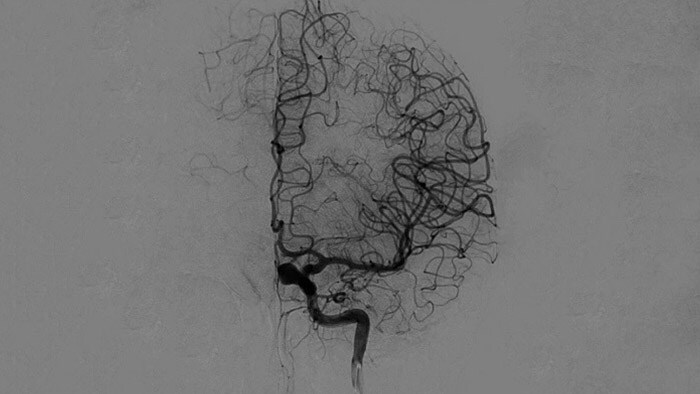

Imágenes nítidas con ASD 2D con tecnología ClarityIQ

ASD 2D con tecnología ClarityIQ

ClarityIQ aplica la compensación automática del movimiento durante la ASD en tiempo real para mantener imágenes nítidas de los vasos. Esto permite tomar decisiones con confianza durante los procedimientos para atender accidentes cerebrovasculares.

Visualización de la ASD

Las visualizaciones de la ASD de alta calidad le permiten evaluar si ha recuperado el coágulo completo y si los trozos de coágulo se han dispersado distalmente en el cerebro. Puede comprobar el restablecimiento del flujo sanguíneo en la penumbra y comprobar si hay hemorragias periprocedimiento.